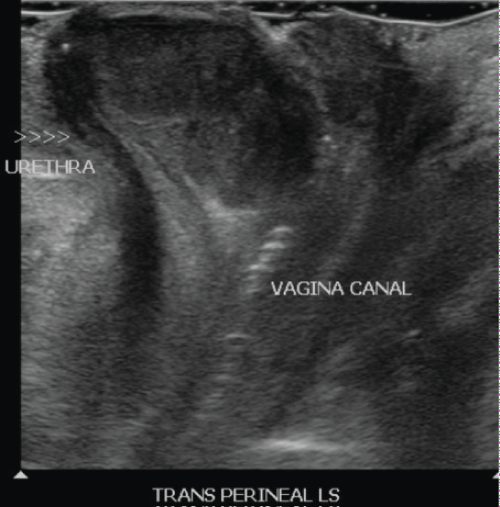

Urine cytology was negative for malignant cells and an ultrasound study of the kidneys and urinary bladder was normal. An ultrasound of the pelvis revealed a 3.1 × 2.5 × 1.5 cm well circumscribed hypervascular hypoechoic mass with a vascular pedicle at the region of the introitus. The vascular stalk appeared to be extending from the vagina. It was seen separate from the urethra. Transperineal ultrasound study was also performed. Overall features were nonspecific and indeterminate. It was suggested that it may be arising from the vagina or could be a prolapsed polyp. The patient was offered two management options - either conservative with a repeat ultrasound pelvis in a few months' time or surgical excision of the vaginal lump. She opted for conservative management.

A repeat ultrasound pelvis three months later revealed a 1 × 0.9 cm endometrial polyp which was not present in the previous study. The anterior vaginal wall mass was largely unchanged from the previous study and now measured 3.5 × 3 × 1.5 cm (Figure 1 and Figure 2). It was again seen separate from the urethra. She was counselled for excision of the vaginal mass and a diagnostic hysteroscopy, polypectomy and endometrial curettage. She consented for the procedure. A metal catheter was inserted into the urethra during the procedure to avoid damage to it during enucleation of the mass. Intraoperatively, a midline vertical incision was made in the anterior vaginal wall over the mass, starting one cm below the urethral orifice and the mass was enucleated. The margins of the mass were very close to the urethral outlet. A check cystourethroscopy performed was normal. The tumour bed was closed using 2-0 vicryl suture and the vaginal mucosa was closed using 2-0 vicryl rapide suture.

Figure 1: Ultrasound picture of anterior vaginal wall mass. View Figure 1

Figure 2: Transperineal view of the mass and it's relation to the urethra. View Figure 2